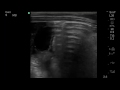

RSV Bronchiolitis Subpleural Consolidation on Mindray TE-X linear array transducer lung preset

6 m.o. Boy RR 40s, subcostal retractions with head bobbing, RSV pcr positive. Lung US using Mindray TE-X linear array transducer detects subpleural consolidation.

Images captured with Mindray TE-X, linear array transducer on lung preset.